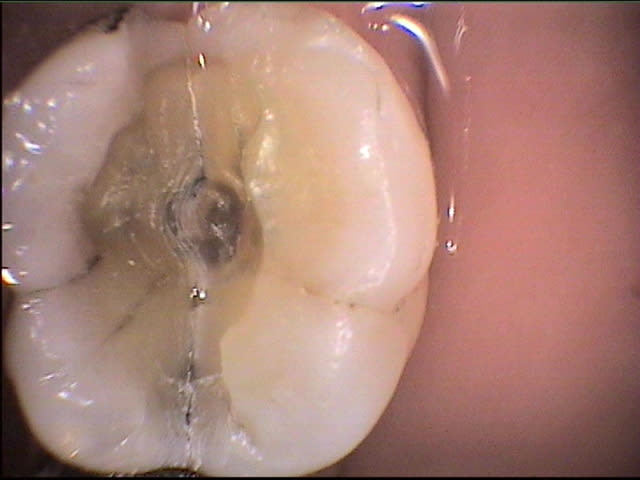

tiens, billi, qu'as-tu fait sur la 46 avec la fêlure MD?

les photos que j'ai mises sur eugenol sont extraites de mes fiches patient "DEMO" et très franchement je ne me souviens pas du cas;ma conduite en général face aux fêlures est 1-essayer de conserver 2-l'expectative ...mise sous provisoire et voir...si pas de signe clinique ou radio.. defnitif...j'aime bien les onlays métal servant de cerclage...le patient est averti;la taille de la fêlure sur la photo n'est pas très encourageante; la caméra révèle bcp de fêlures qu'on ignore